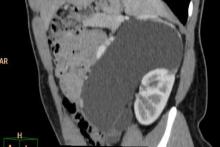

Pacjentka została przyjęta do Szpitala, wykonano nieskuteczną próbę odgłobienia wlewem wodnym pod kontrolą USG (biała strzałka - wgłobienie, pomarańczowe strzałki - płyn w jelicie grubym). Pacjentka operowana - stwierdzono wgłobienie patologiczne, z uchyłkiem Meckela jako punktem prowadzącym.